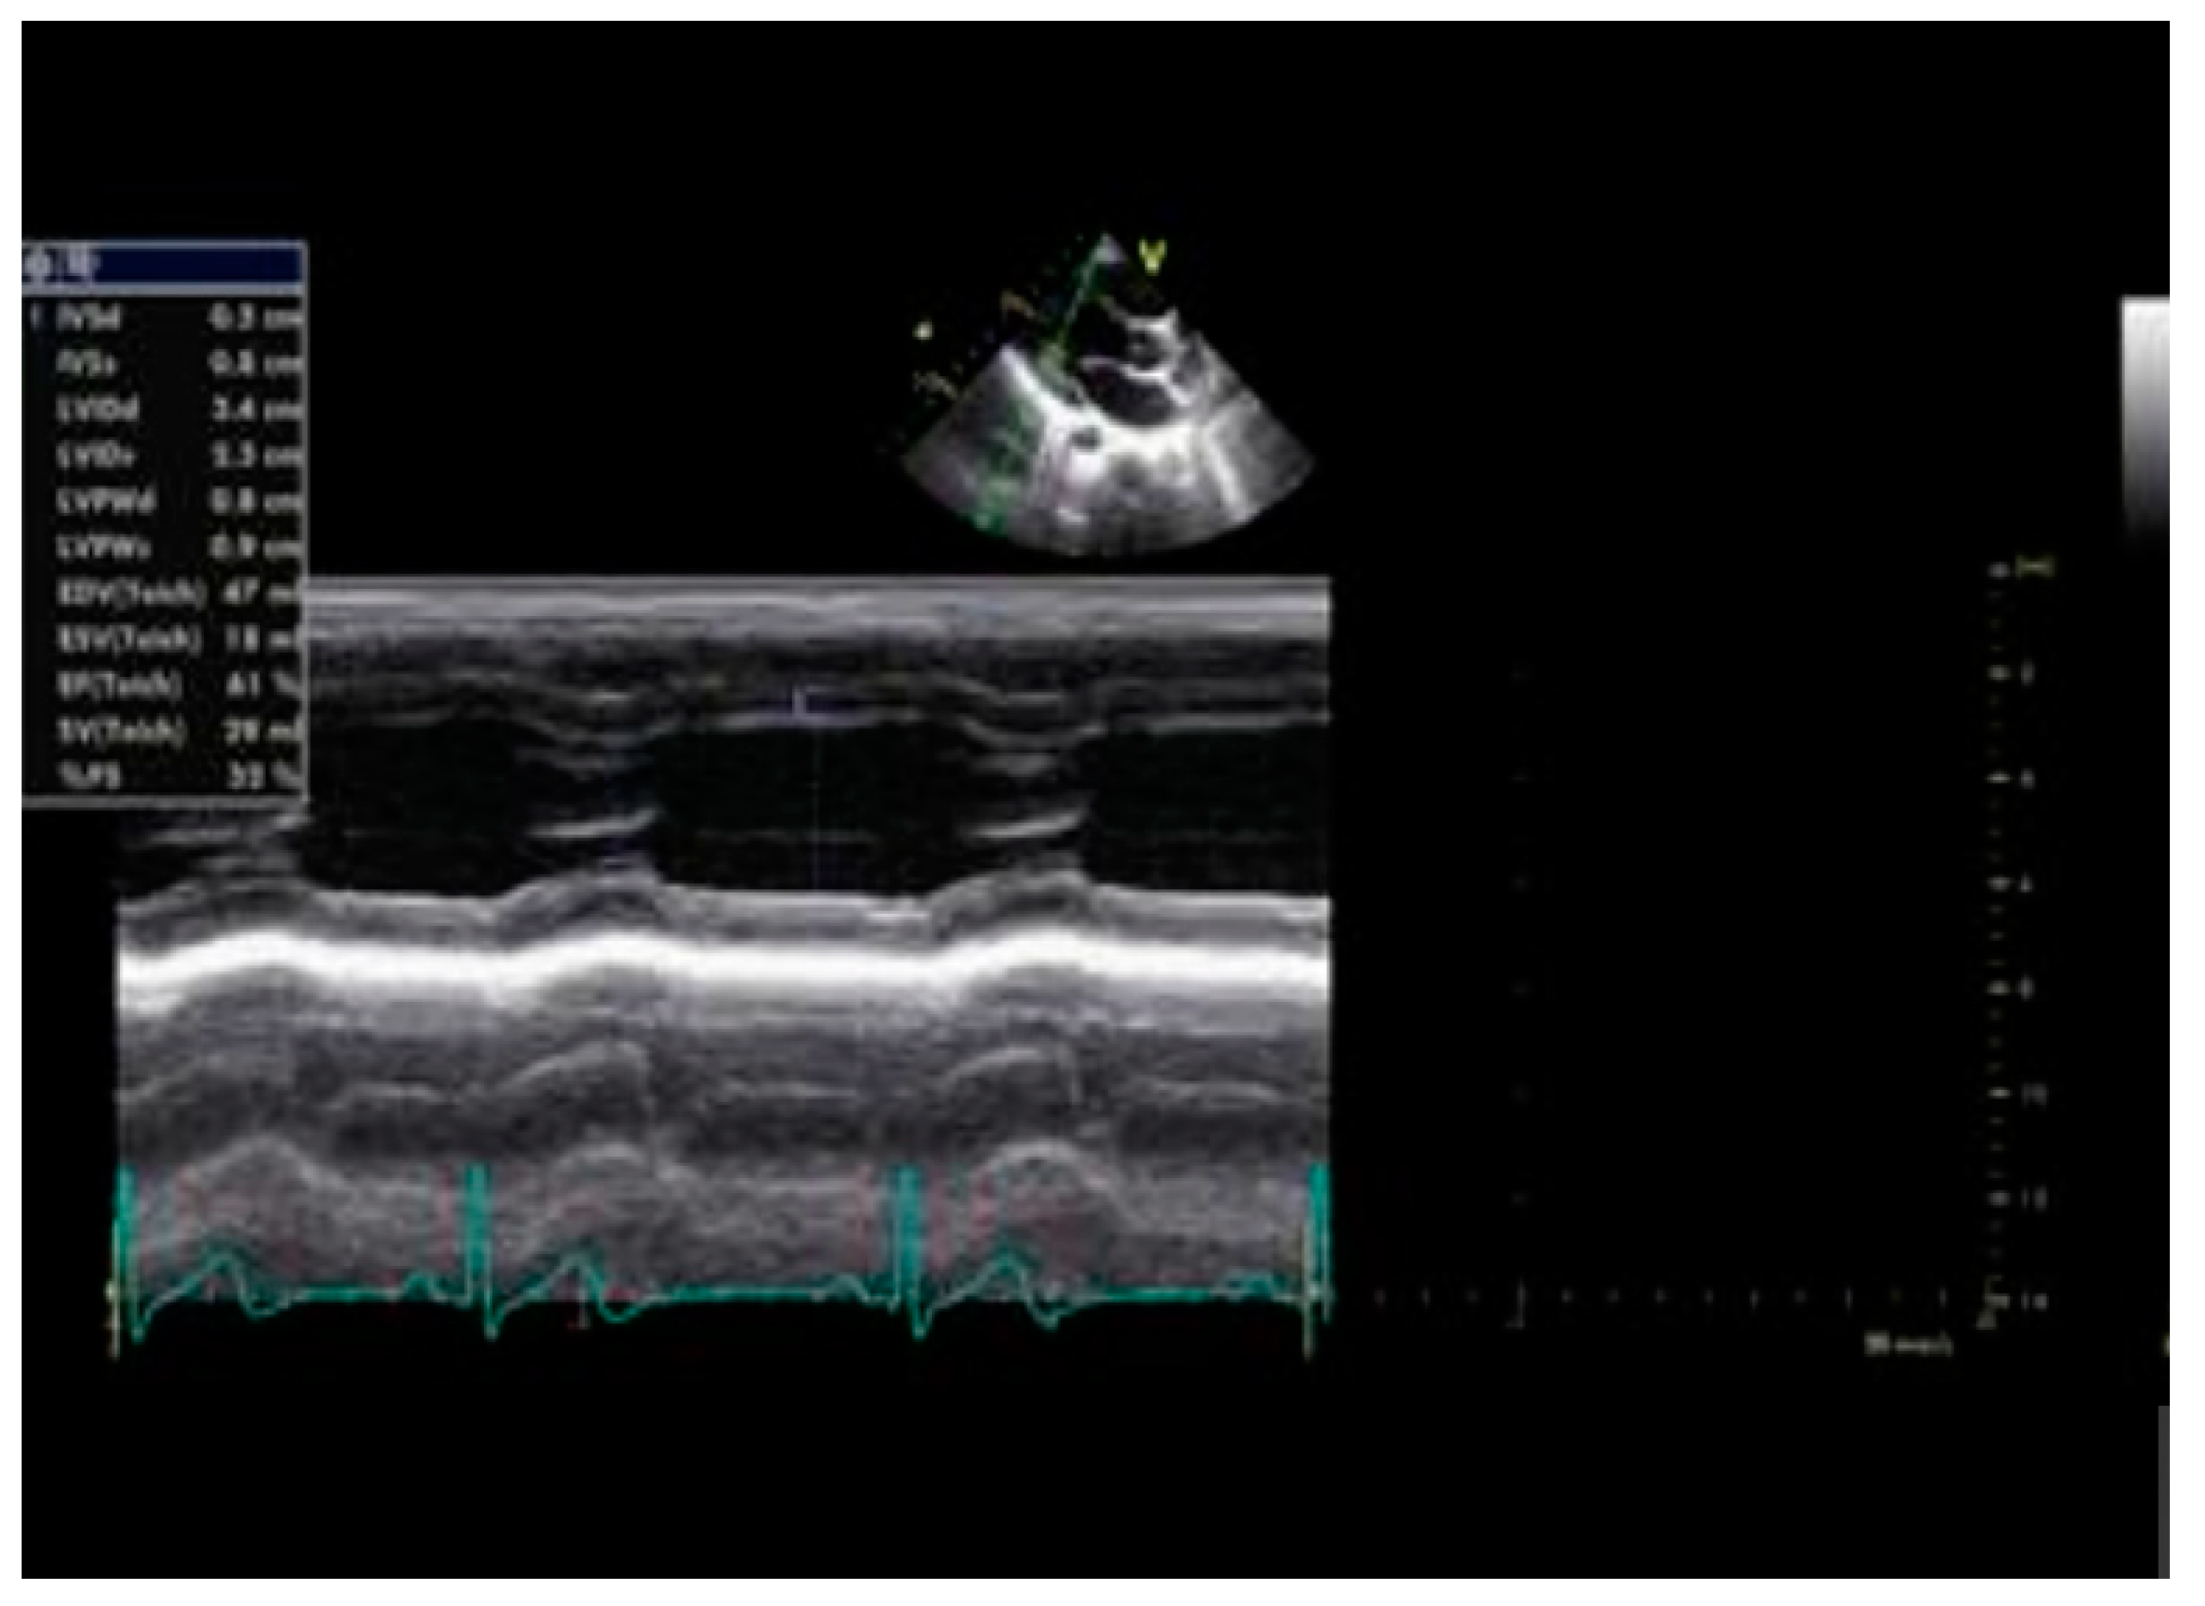

2.2. Echocardiography